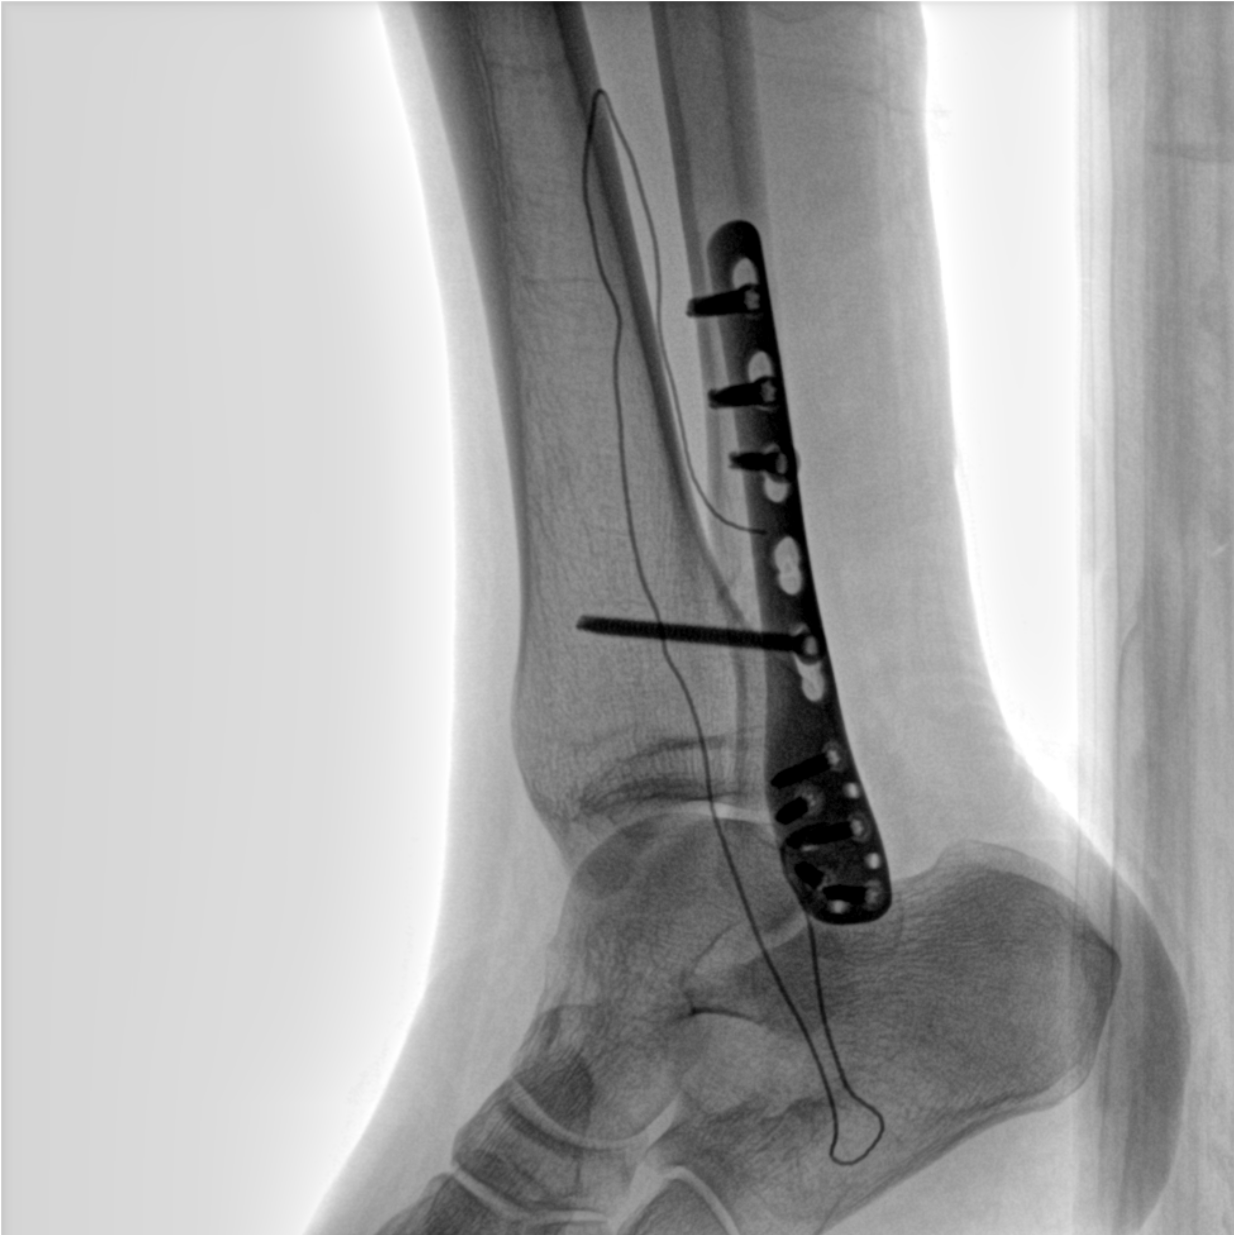

術(shù)中三維成像和橫斷面圖像提供多角度的手術(shù)診斷信息,輔助醫(yī)生進(jìn)行術(shù)中評估判斷,諸如骨折復(fù)位情況和內(nèi)植入螺釘?shù)某叽绾臀恢茫o助手術(shù)更好地完成。